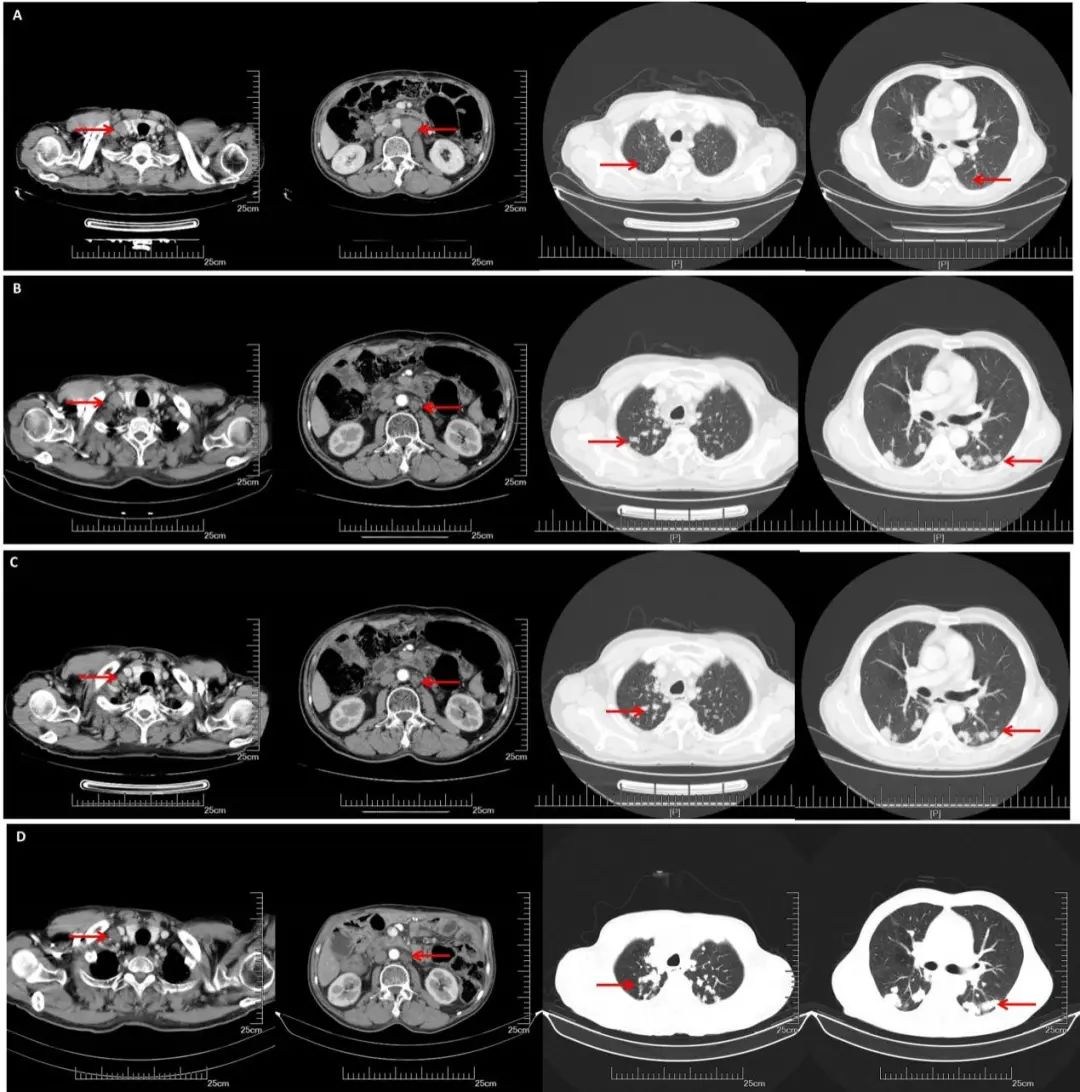

CT(2019. 5.16):双侧锁骨上、双侧膈肌脚后间隙、脊柱左旁及纵隔多发淋巴结,部分较前增大:腹膜后及右侧髂血管旁多发淋巴结,部分较前减小。余较前相仿。双肺多发转移瘤。较前增多增大。

CT(2019.10.25):双肺多发转移结节,较前明显增多增大。双侧锁骨上、双侧膈肌脚后间隙、脊柱左旁、纵隔多发肿大淋巴结,较前变化不明显。

CT(2020.05.27):双肺多发转移瘤,较前大致相仿。双侧锁骨上、双侧膈肌脚后间隙、脊柱左旁、纵隔、腹腔、腹膜后及右侧髂血管旁等多发淋巴结,部分肿大,较前大致相仿。

A:CT增强(2018.11.07): 腹膜后多发淋巴结转移,部分较前增大。双侧锁骨上淋巴结转移,部分较前增大,双肺多发结节,转移可能;B:CT增强(2019.05.16):腹膜后淋巴结较前缩小,双肺转移较前增多增大;C:CT增强(2019.10.25):腹膜后淋巴结稳定,双肺转移较前增多增大;D:CT增强(2020.05.27):双肺转移瘤及腹腔淋巴结总体稳定。